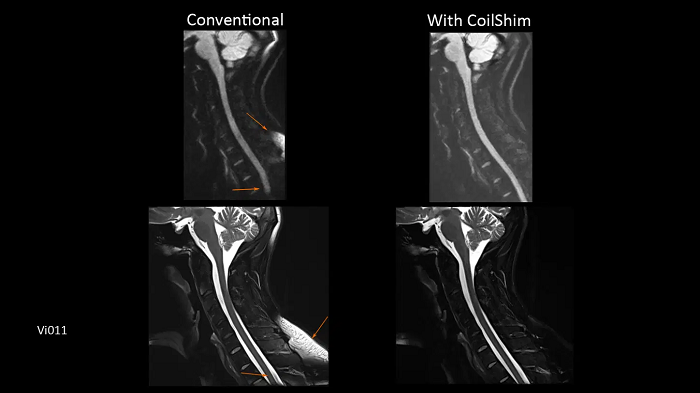

C-spine imaging with and without CoilShim

The groundbreaking CoilShim technology incorporates shim components into the new BioMatrix Head/Neck coils, enabling patient and region-specific shimming for dramatically increased fat saturation and DWI quality.

- BioMatrix Head/Neck 20 (18° tilt)

Image Credit: Siemens Healthineers

BioMatrix SliceAdjust

Prevent broken spine artifacts in the whole spine DWI